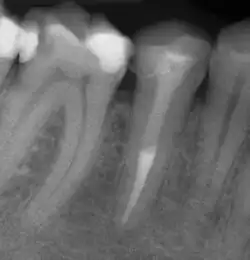

Zur Beurteilung des Erfolges einer Wurzelkanalbehandlung werden klinische Beschwerden, wie Schmerzen, Schwellungen oder Fistelgänge sowie der röntgenologische Befund herangezogen. Oft sind trotz endodontischer Infektion keine klinischen Beschwerden vorhanden, weshalb gerade die röntgenologische Kontrolle Hauptkriterium für die Beurteilung ist.[10] Neben der vorhandenen Wurzelfüllung und Veränderungen in der Wurzelphysiognomie (Resorptionen) wird vor allem der Zustand des periapikalen Gewebes begutachtet und auf das Vorhandensein einer Parodontitis apikalis oder einer radikulären Zyste geprüft.

Wenn eine Verbesserung des Ausgangszustandes und eine Beseitigung der möglichen Ursachen nicht zu erwarten sind oder die Erhaltung des Zahns fragwürdig ist, ist von einer Revision abzusehen. Ebenso müssen nicht-endodontische Ursachen der Erkrankung vor einem Eingriff ausgeschlossen werden.[1] Nach Strindberg et al. wird der endodontische Misserfolg nach einer ausreichenden Heilungszeit von vier Jahren mit dem Vorhandensein einer residuellen, persistierenden oder progredienten röntgenologischen Aufhellung (Dunkler Punkt an der Wurzelspitze im Röntgenbild) und/oder mit dem Vorhandensein klinischer Beschwerden jeglicher Form definiert.[18]